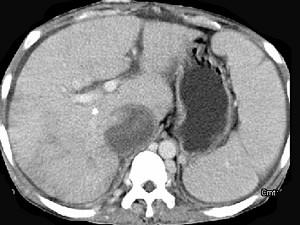

问题 女性,26岁,腹胀不适7月,腹软,肝右肋缘下1cm,影像检查如图,可能的诊断为 ( )

选项 A、布加综合征 B、脂肪肝 C、原发性肝癌 D、肝硬化腹水 E、肝血管瘤

答案 A